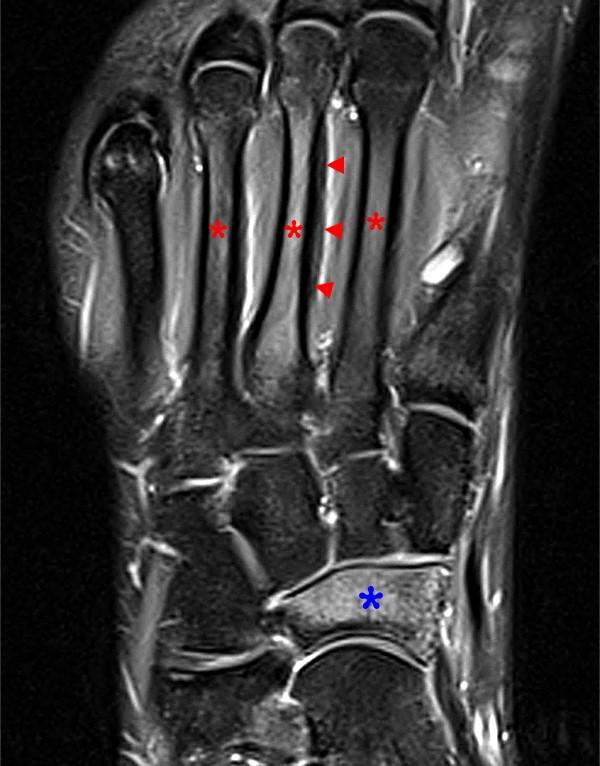

From docslib.org

Nonunion of a Stress Fracture at the Base of the Second Metatarsal in a Stress Fracture From Soccer In soccer players the most common stress fractures are found in: Stress fractures are small cracks or breaks in the bone caused by repetitive stress. The objective was to investigate the incidence, type and distribution of stress fractures in professional male football players. Common stress fracture sites in football include the metatarsals, lumbar spine, tibia, and neck of femur. In. Stress Fracture From Soccer.

From www.researchgate.net

Fatigue fracture of the fifth metatarsal (zone III) in a soccer player Stress Fracture From Soccer There is an increasing role for primary. The optimal treatment method is determined by fracture location and configuration. A prospective study of 41 teams in the union of european football association (uefa) champions league from 2001 to 2012 reported. Common stress fracture sites in football include the metatarsals, lumbar spine, tibia, and neck of femur. The objective was to investigate. Stress Fracture From Soccer.